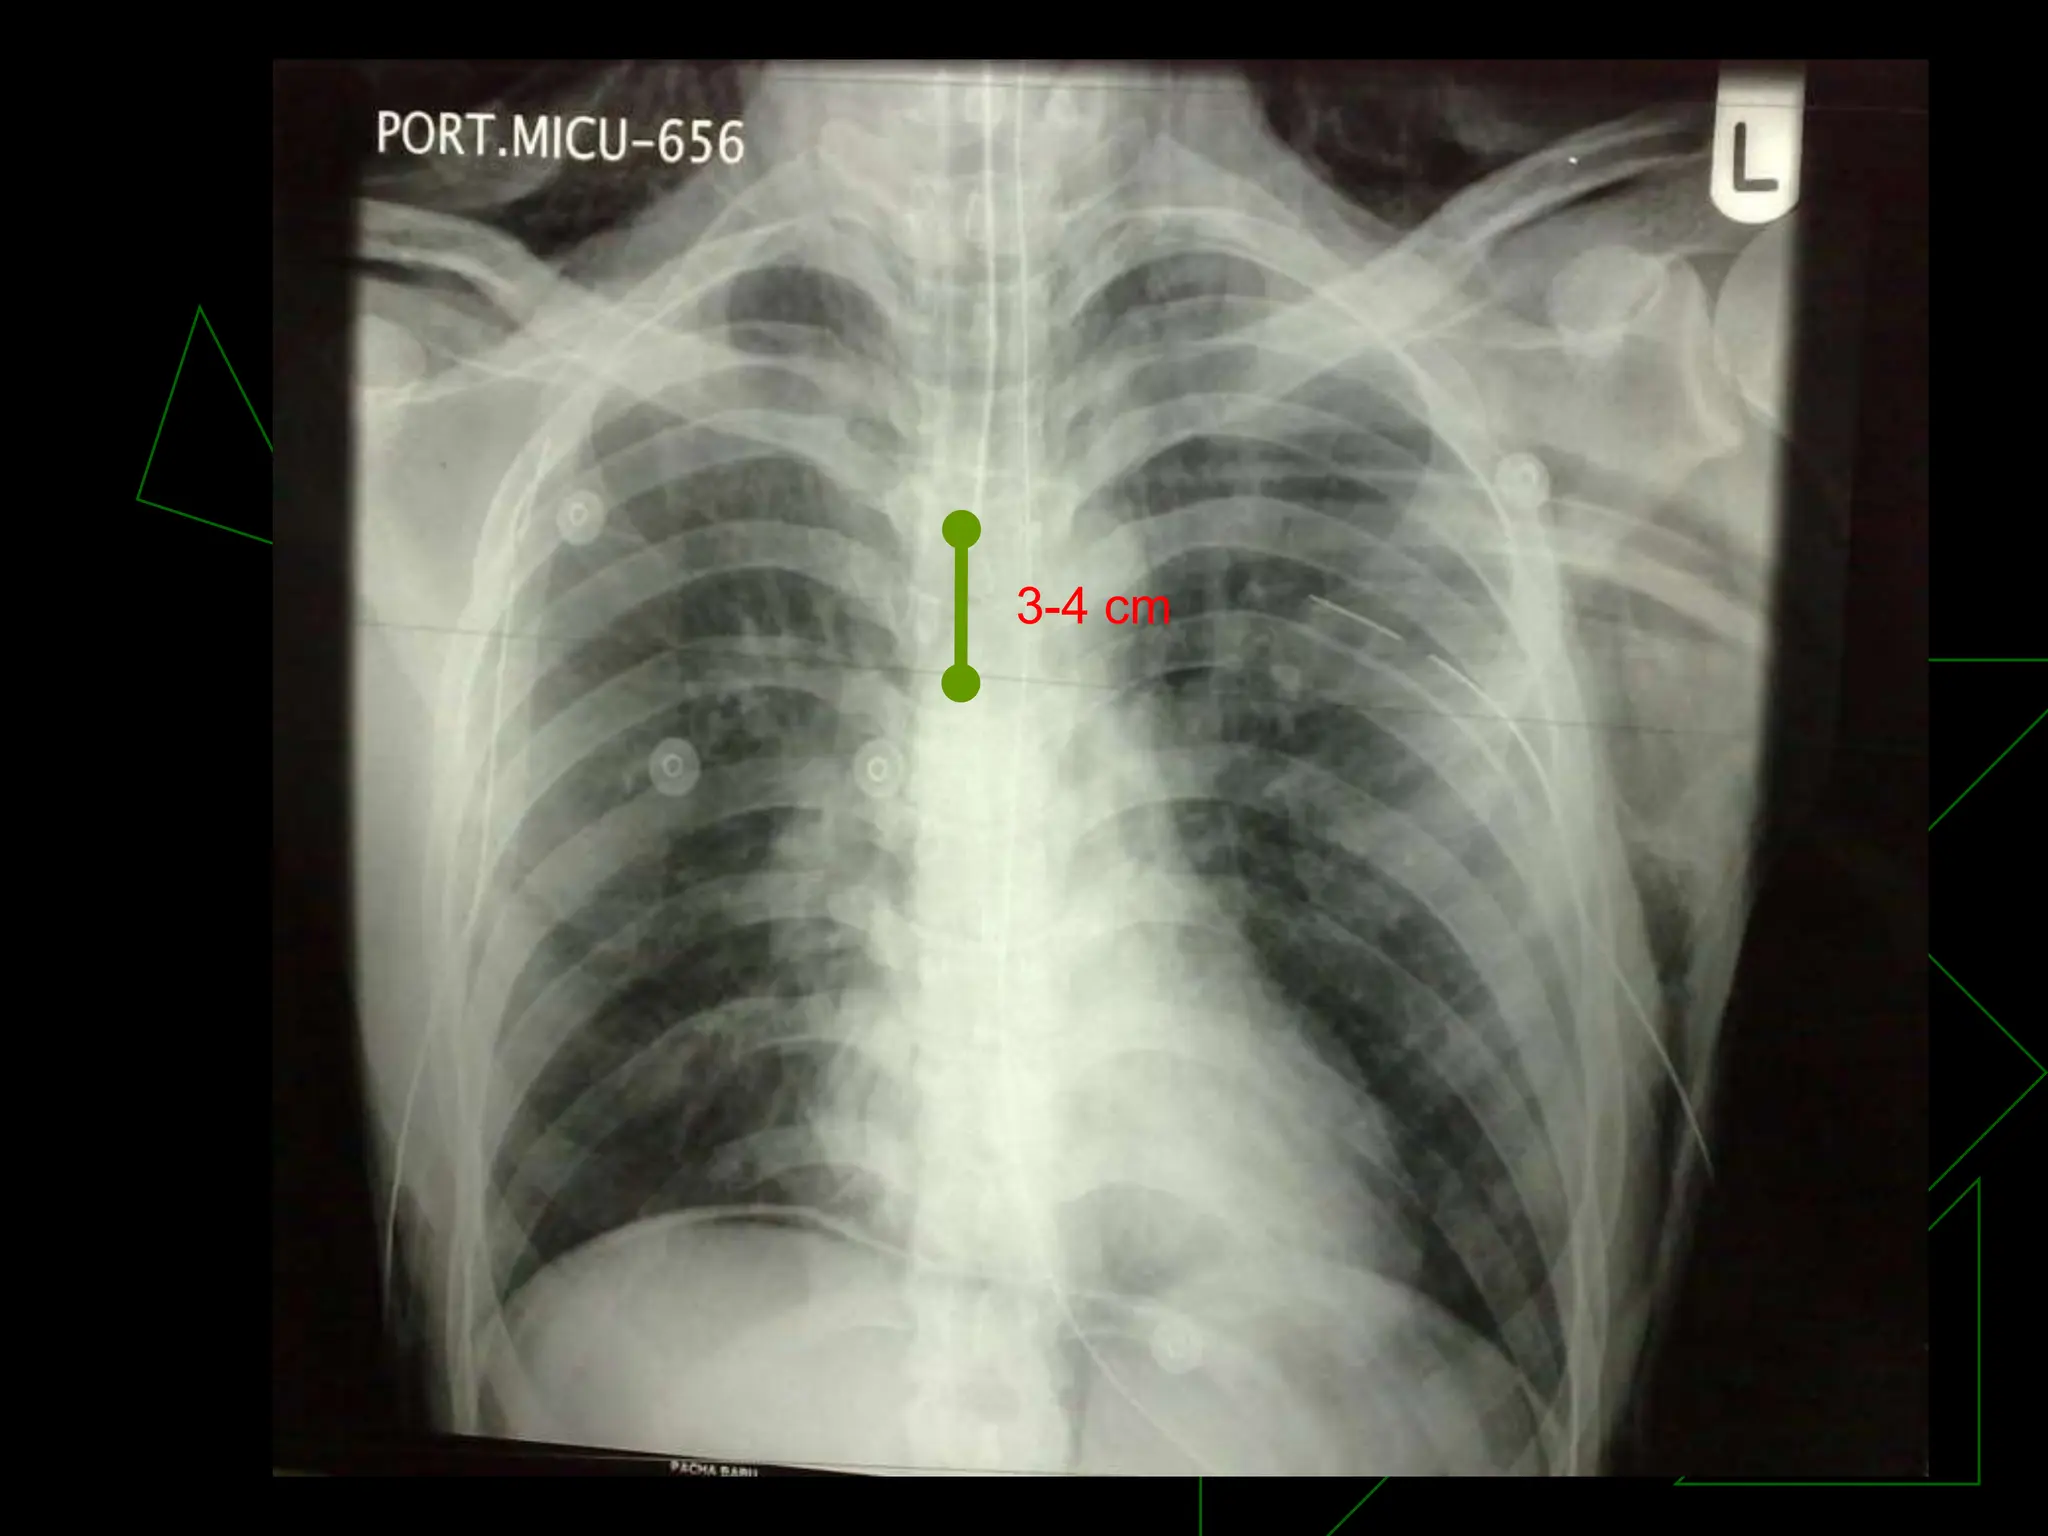

Correct ET Tube Placement:

Capnography

Purpul Yellow

3-4 cm

Correct ET Tube

Placement

Correct ET TubePlacement: Capnography Purpul Yellow